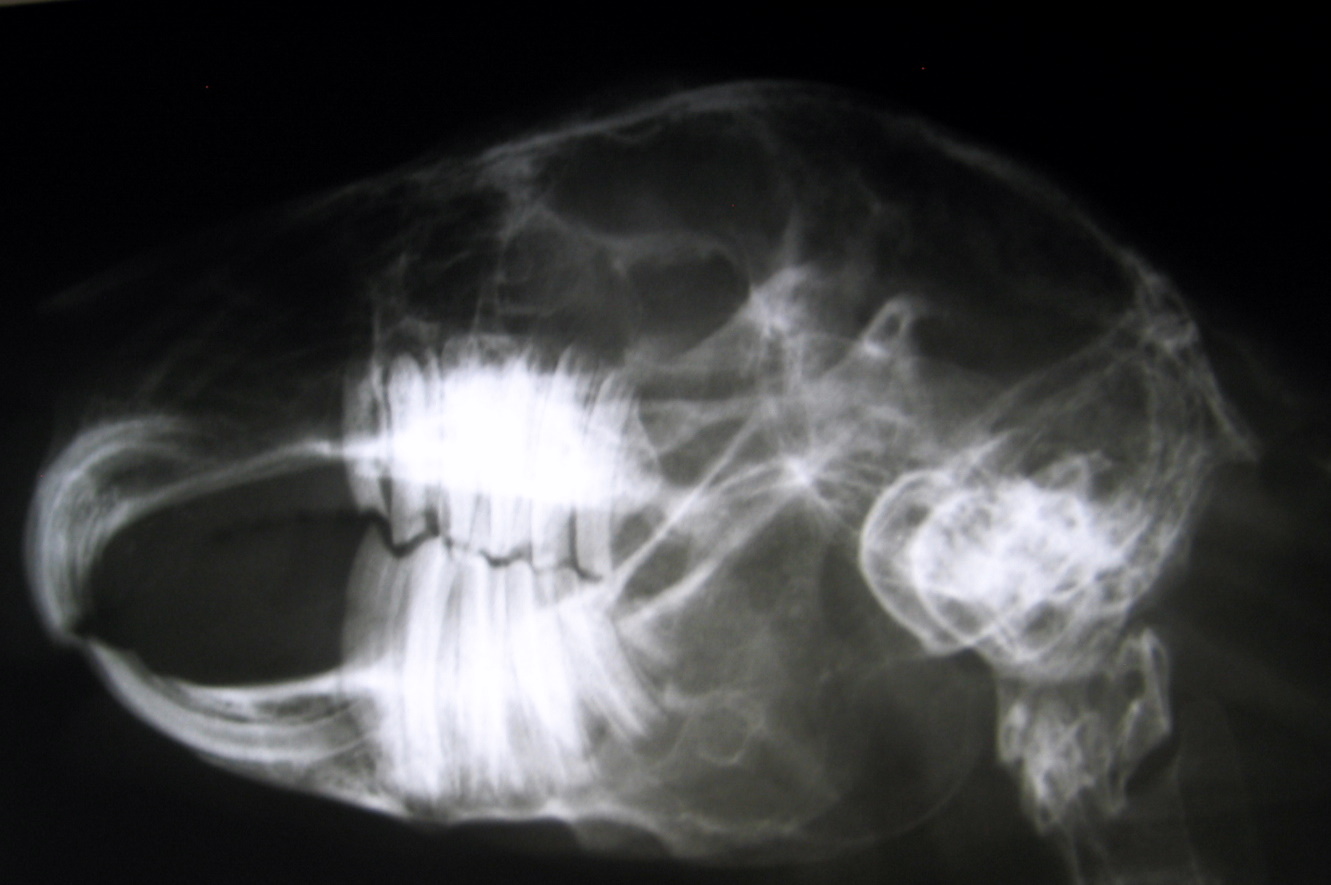

Um eine Zahnerkrankung diagnostizieren zu können , muss die Maulhöhle sorgfältig untersucht werden. Ein exakter Überblick kann jedoch nur unter Sedierung / Narkose des Tieres erfolgen. Sollten sich Zahnspitzen oder Fehlstellungen finden, müssen Röntgenbilder angefertigt werden. Überwachsene Scheidezähne werden mit einer Trennscheibe / Fräser gekürzt. Das Abknipsen mit einer Zange führt meist zum Splittern der Zähne und sollte vermieden werden. Spitzen und Kanten an den Backenzähnen sowie überwachsene Backenzähne werden mit einer speziellen Fräse abgeschliffen.